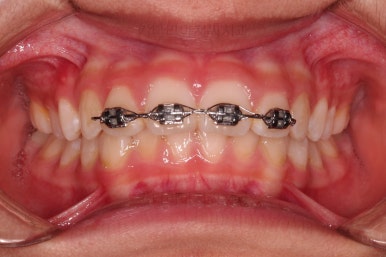

트윈블락 장치와 더불어 윗니 앞니는 가지런하게 하기 위해서 브라켓-철사 장치가 부분적으로 들어갔는데요.

아래턱이 성장하기 위해서 너무 삐뚠 윗니 앞니는 아래턱이 앞으로 나오는 걸 방해하기 때문에 부분적으로 부착형 장치를 쓸 수 밖에 없는 상황이었습니다.

윗니에 들어가는 장치는 악궁확장 기능도 들어가 있어서 위턱을 넓히며 아래턱을 앞으로 내어주는 3차원적인 조절이 가능했습니다.

어금니 맞물림 등 전반적으로 매우 좋아졌습니다.

대신 트윈블락은 위아래 어금니를 서로 정교하게 잡아주는 역할을 하지는 않기 때문에 약간 맞물림이 엉성하게 마무리 될 수 있어서 2차교정(치열교정)으로 자연스럽게 넘어가는 경우가 많습니다.

하지만 이번 환자분은 맞물림은 약간 엉성하긴 하지만 2차교정까지는 선택 사항일 정도로 치열 등 나쁘지 않은 모습이었는데요.